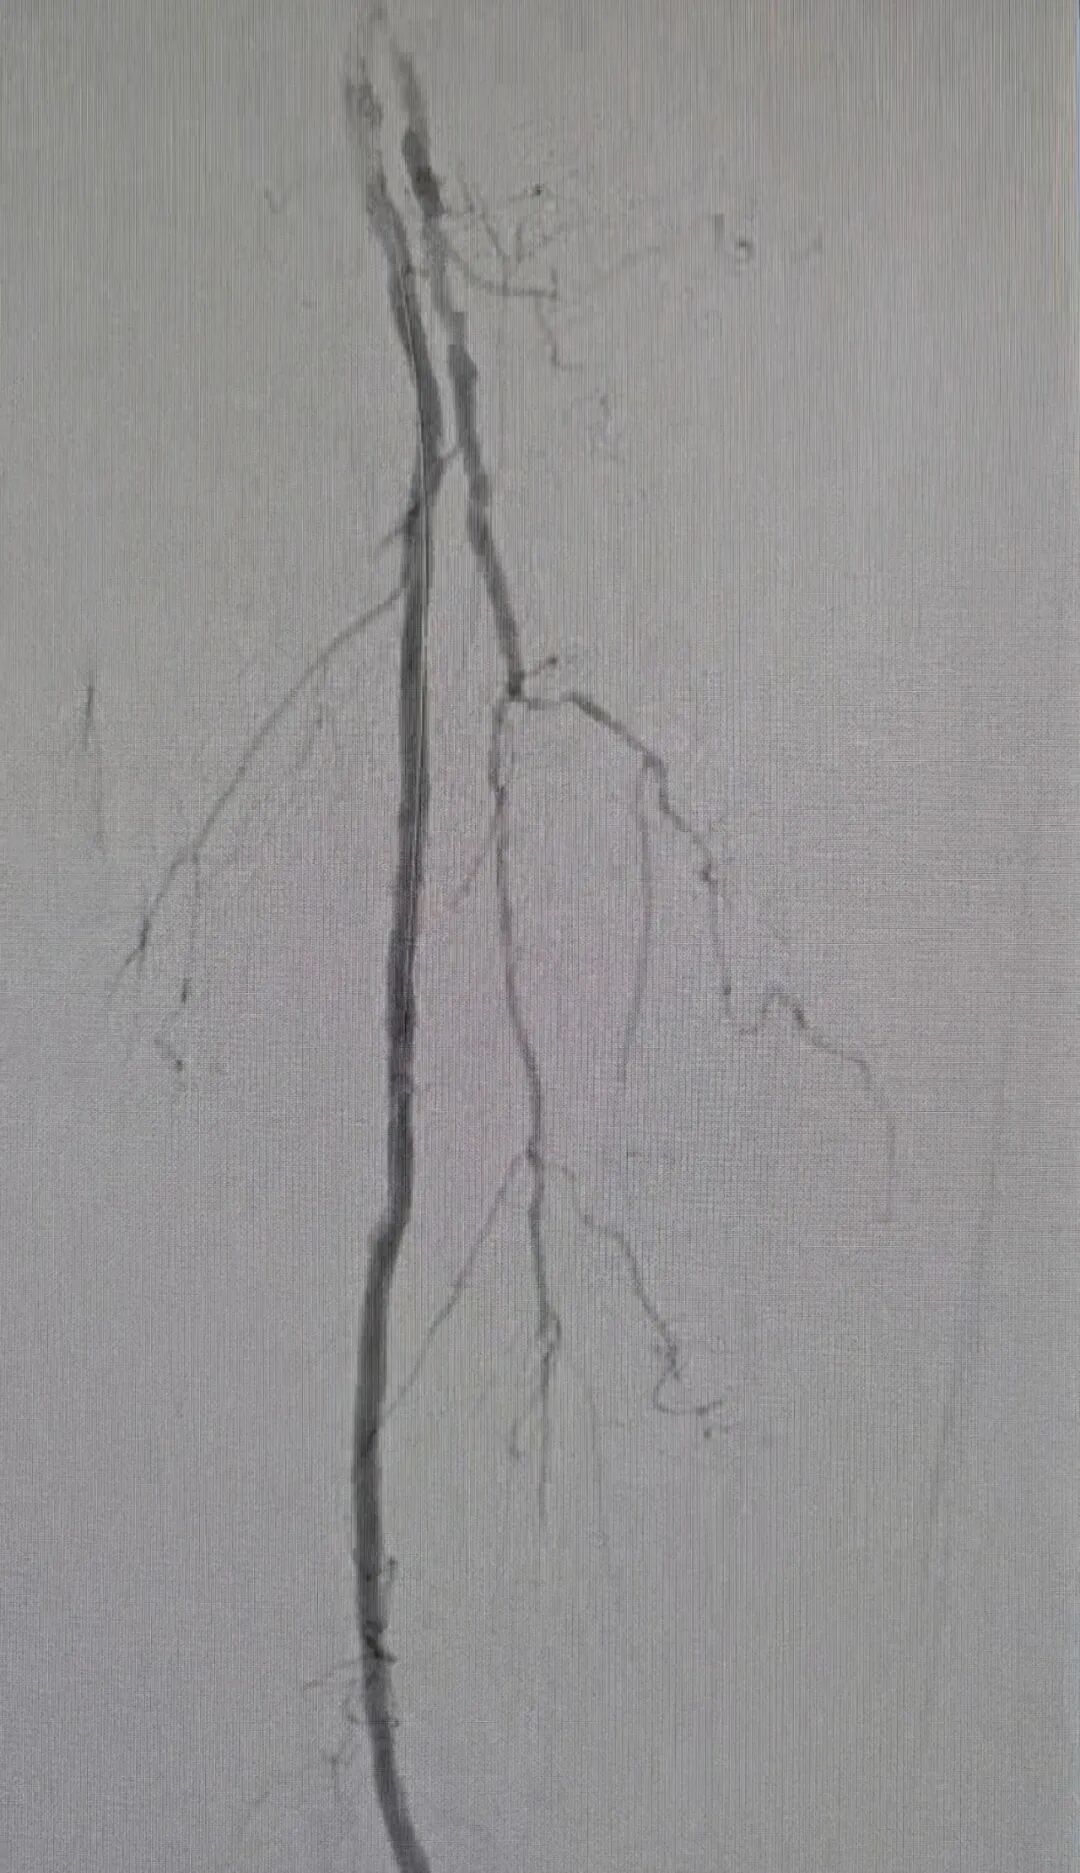

为保障手术安全,科室开展多学科评估,结合患者高龄身体特点制定个体化无植入微创方案,决定采用先进斑块旋切技术。术中在DSA造影精准导航下,医生通过针眼大小穿刺建立通路,将旋切导管送入闭塞血管内,如同血管内的微型盾构机,利用高速旋切装置精准切削、研磨顽固钙化斑块,同步负压抽吸清除斑块碎屑,从源头剥离堵塞病灶,还原原生血管管腔,随后优化血管管腔,重建下肢供血通道。

术后造影显示,患者闭塞动脉血流通畅,血流直达肢体远端,无血管夹层、远端栓塞等并发症。老人下肢皮温快速回升,疼痛麻木感缓解,足部血供恢复良好。